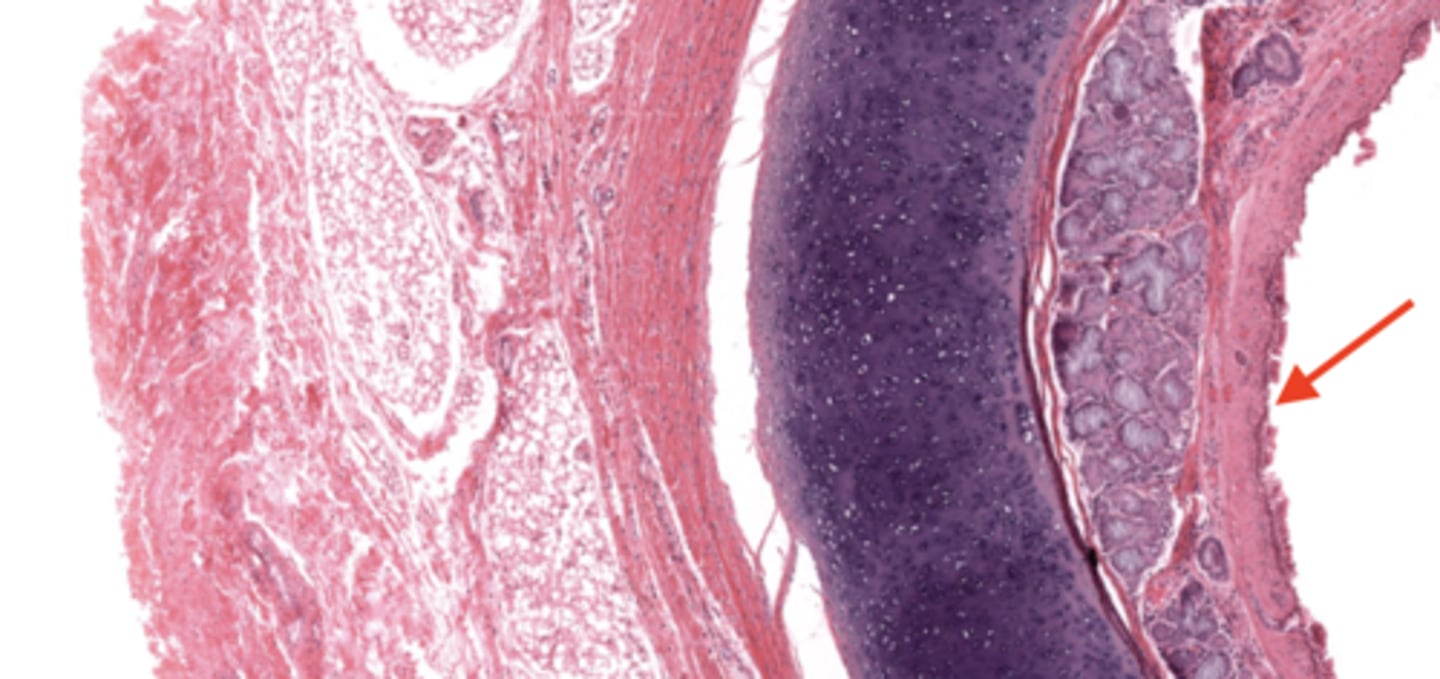

smoker's lung

alveolus (of smoker's lung)

carbon deposits (tar)